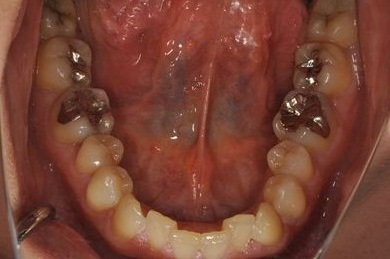

| 治療方針 | 上顎前歯、抜歯と同時にインプラントを埋入し、治療期間を短縮する。 | ||||||||||||||||||||||||||||||||

| 治療内容 | インプラント2本、メタルボンドセラミッククラウン2本 | ||||||||||||||||||||||||||||||||